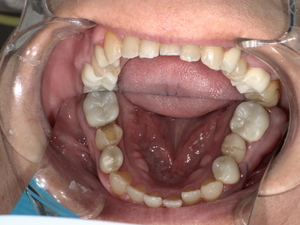

診察の結果、脱落した詰め物の周囲だけでなく、隣接する歯との適合性も著しく低下していました。

二次虫歯(再発虫歯)の進行: 詰め物と歯の隙間から菌が入り込み、内部で虫歯が広がっていました。

歯周病リスクの増加: 段差がある箇所にプラーク(歯垢)が溜まりやすく、歯茎の炎症を引き起こしていました。

噛み合わせの不調: 詰め物が欠けた状態で放置されていたため、反対側の歯に負担がかかっていました。

このまま「その場しのぎの補修」を繰り返しても、数年後にまた再発する可能性が高いと判断し、「精度」「耐久性」「審美性」のすべてを満たすジルコニアセラミッククラウンをご提案しました。

After: セラミックで修復され、天然歯のように自然な白さと透明感がある美しい歯の状態。どこが治療箇所か分からないほど自然な白さへ。